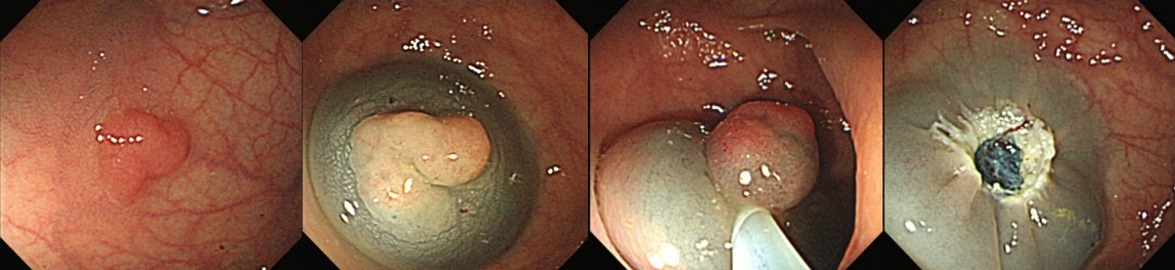

『大腸ポリープ切除術(EMR)』

大腸ポリープ切除術、早期癌に対する内視鏡的粘膜剥離術、胃潰瘍などからの出血に対する内視鏡的止血術、食道静脈瘤からの出血に対する結紮術、アニサキス(寄生虫)や薬パッケージの誤飲に対する異物摘出術など。また胆道・膵臓系では、内視鏡を用いた胆石除去や、胆道感染や癌に伴う黄疸に対する内視鏡的な減黄術(ステント留置術)など各種行っております。